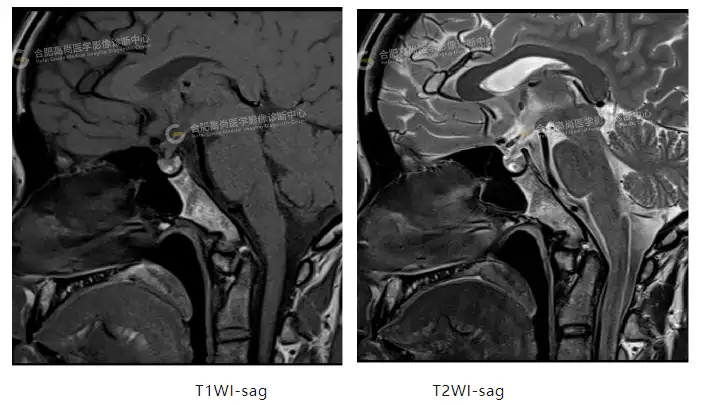

影像表现:垂体形态饱满,上下径约7mm,垂体柄增粗,厚约2.4mm,垂体柄大致居中,垂体前叶中央可见一类圆形异常信号影,边界清,大小约4mmx3mm,T1WI呈高信号,T2WI呈高低混杂信号,病灶中央呈低信号,增强扫描病灶信号早期低于垂体,延迟强化,后期等于垂体,表现为明显“慢进慢出”延迟强化。垂体后叶呈高信号,其内未见异常密度信号,增强扫描垂体后叶及垂体柄未见异常强化。视交叉及海绵窦未见受压。斜坡骨质未见明显异常。

影像诊断:垂体前叶异常信号,考虑垂体微腺瘤。

垂体微腺瘤常局限于垂体窝或两侧海绵窦旁,形态以圆形或类圆形为主,少数可表现为平铺在鞍底的扁平状病灶。T1WI 为低信号或等信号;T2WI 以等信号和稍高信号为主(病灶中的小囊变可表现为明显高信号),但也可表现为低信号。强化方式为“慢进慢出”,与早期明显强化的正常垂体组织形成对比,表现为低强化改变[1]。